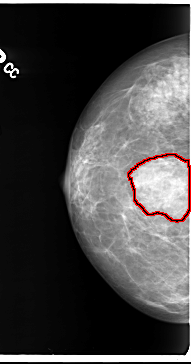

B_3101_1.RIGHT_CC

RIGHT_CC LINES 4720 PIXELS_PER_LINE 2472 BITS_PER_PIXEL 12 RESOLUTION 50 OVERLAY

FILE: B_3101_1.RIGHT_CC.OVERLAY

TOTAL_ABNORMALITIES 1

ABNORMALITY 1

LESION_TYPE MASS SHAPE IRREGULAR-FOCAL_ASYMMETRIC_DENSITY MARGINS ILL_DEFINED

ASSESSMENT 3

SUBTLETY 4

PATHOLOGY BENIGN

TOTAL_OUTLINES 1

BOUNDARY